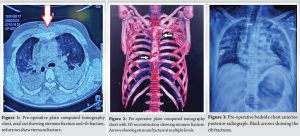

A 43-year-old man with a history of a road traffic accident arrived at the trauma and emergency department. On initial assessment, the patient was conscious and hemodynamically stable but complained of severe chest pain and pain in the right lower limb. Primary and secondary surveys were conducted according to the advanced trauma life support protocol. Clinical examination, an open wound was noted on the proximal right tibia with visible bone fragments, suggesting a Grade IIIB open fracture.. There was noticeable limb deformity, abnormal mobility, and crepitus at the fracture site. The affected limb was neurovascularly intact distally. Accompanied by severe chest pain, especially in the mid-sternum region, along with a chest wall deformity. Palpation elicited tenderness over the mid-sternum. The chest compression test was positive. Crepitus was present over the left lateral chest wall, and there was pain radiating to the sternum on movement of both glenohumeral joints. However, a full range of motion was preserved. Breath sounds were reduced on the left side. After stabilization, computed tomography (CT) (Fig. 1, 2) and a plain chest X-ray (Fig. 3) scan of the chest were performed. These imaging studies showed a fracture in the proximal one-third of the tibia shaft with an open wound on the medial side, a transverse fracture of the corpus divided into three fragments, and two associated rib fractures. Following initial stabilization, an intercostal drainage tube was placed on the left side of the chest, and the patient was monitored overnight in the critical care unit. Surgery was indicated due to severe deformity with dislocated and overlapping sternal edges. The primary goal was to restore anatomical alignment, ensure chest wall stability, and prevent complications such as chronic nonunion or restrictive pulmonary dysfunction.